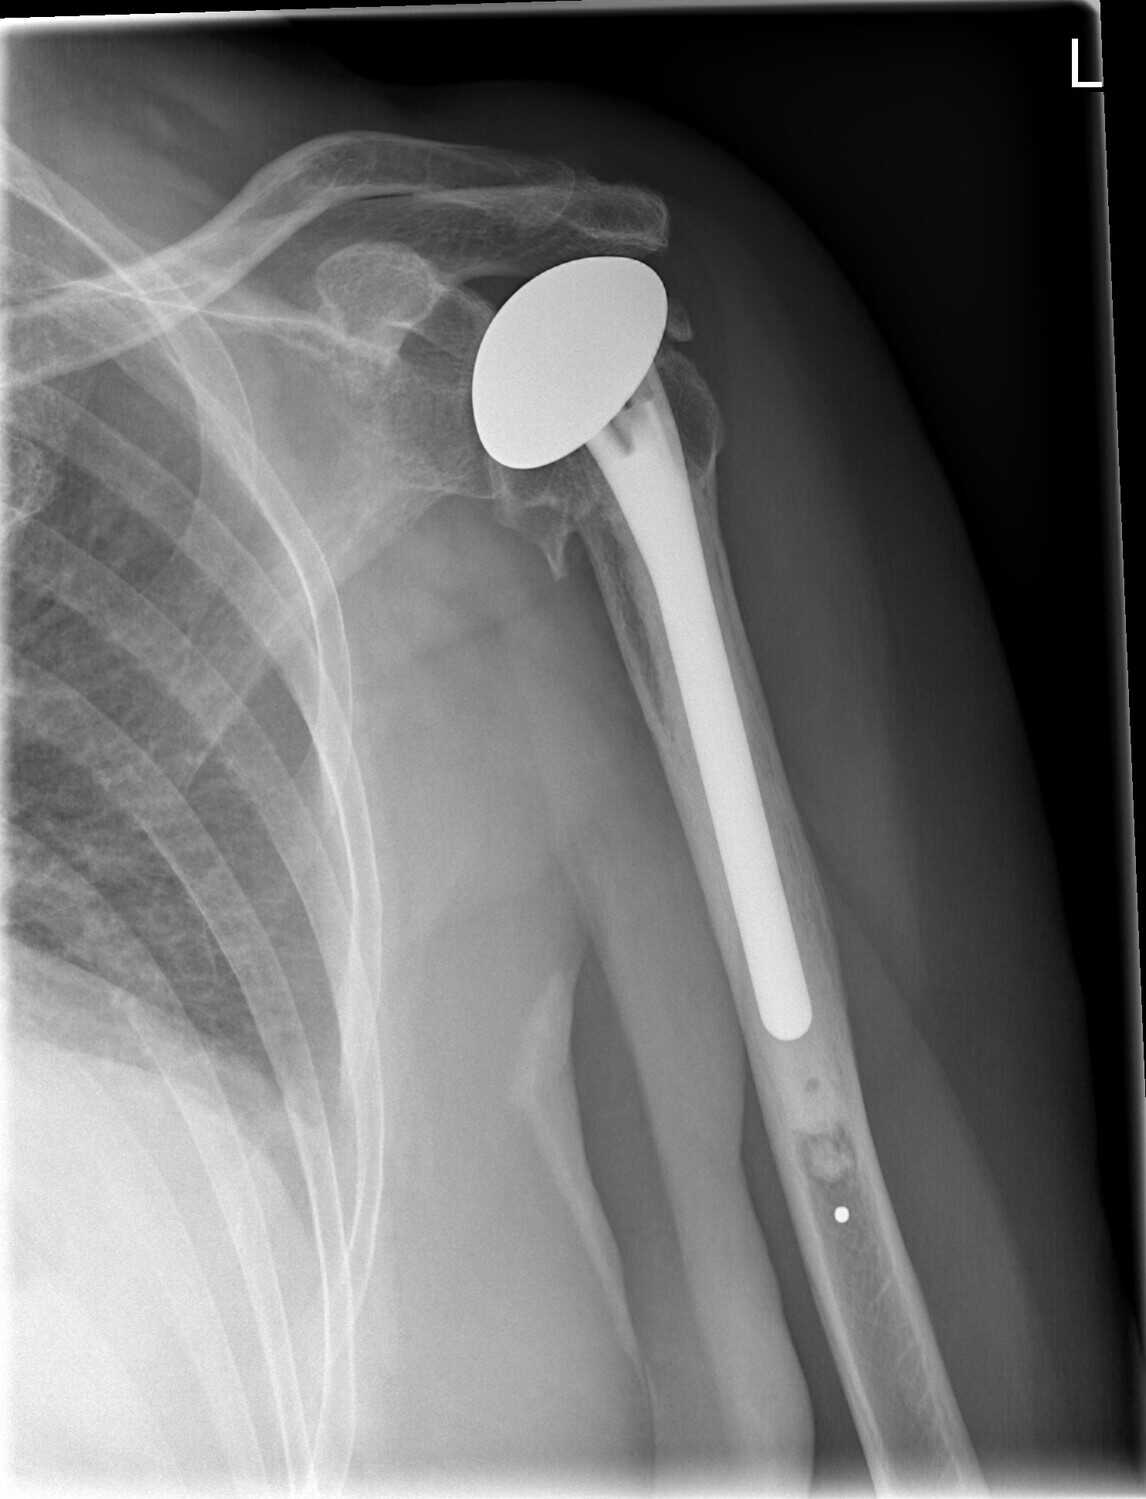

Film X ray shoulder show shoulder joint prosthesis. The patient has What Is A Partial Shoulder Replacement Only the ball gets replaced. Usually, you'd get this if you have. In others, the bone in the socket is too worn out. What is partial shoulder replacement? Partial shoulder replacement, also known as hemiarthroplasty, involves replacing only the. This surgery involves just the partial replacement of the injured shoulder’s parts. A shoulder replacement is a procedure that tries to. What Is A Partial Shoulder Replacement.